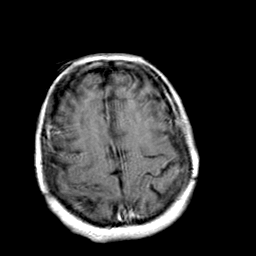

Creutzfeld-Jakob disease: gadolinium enchanced T1-Weighted MR -- Slice #18

[Home][Help][Clinical] Slice 18